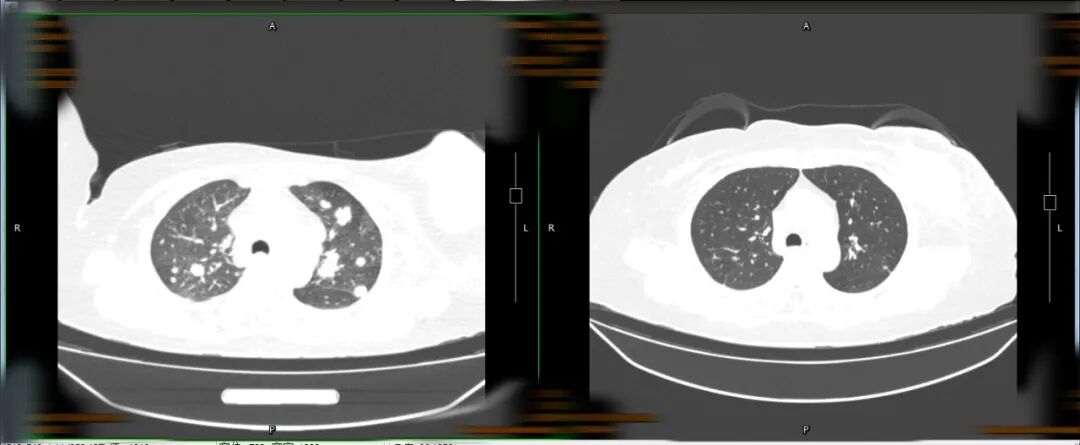

王婆婆2022年7月2日入院

与2023年7月19日肺部CT对比